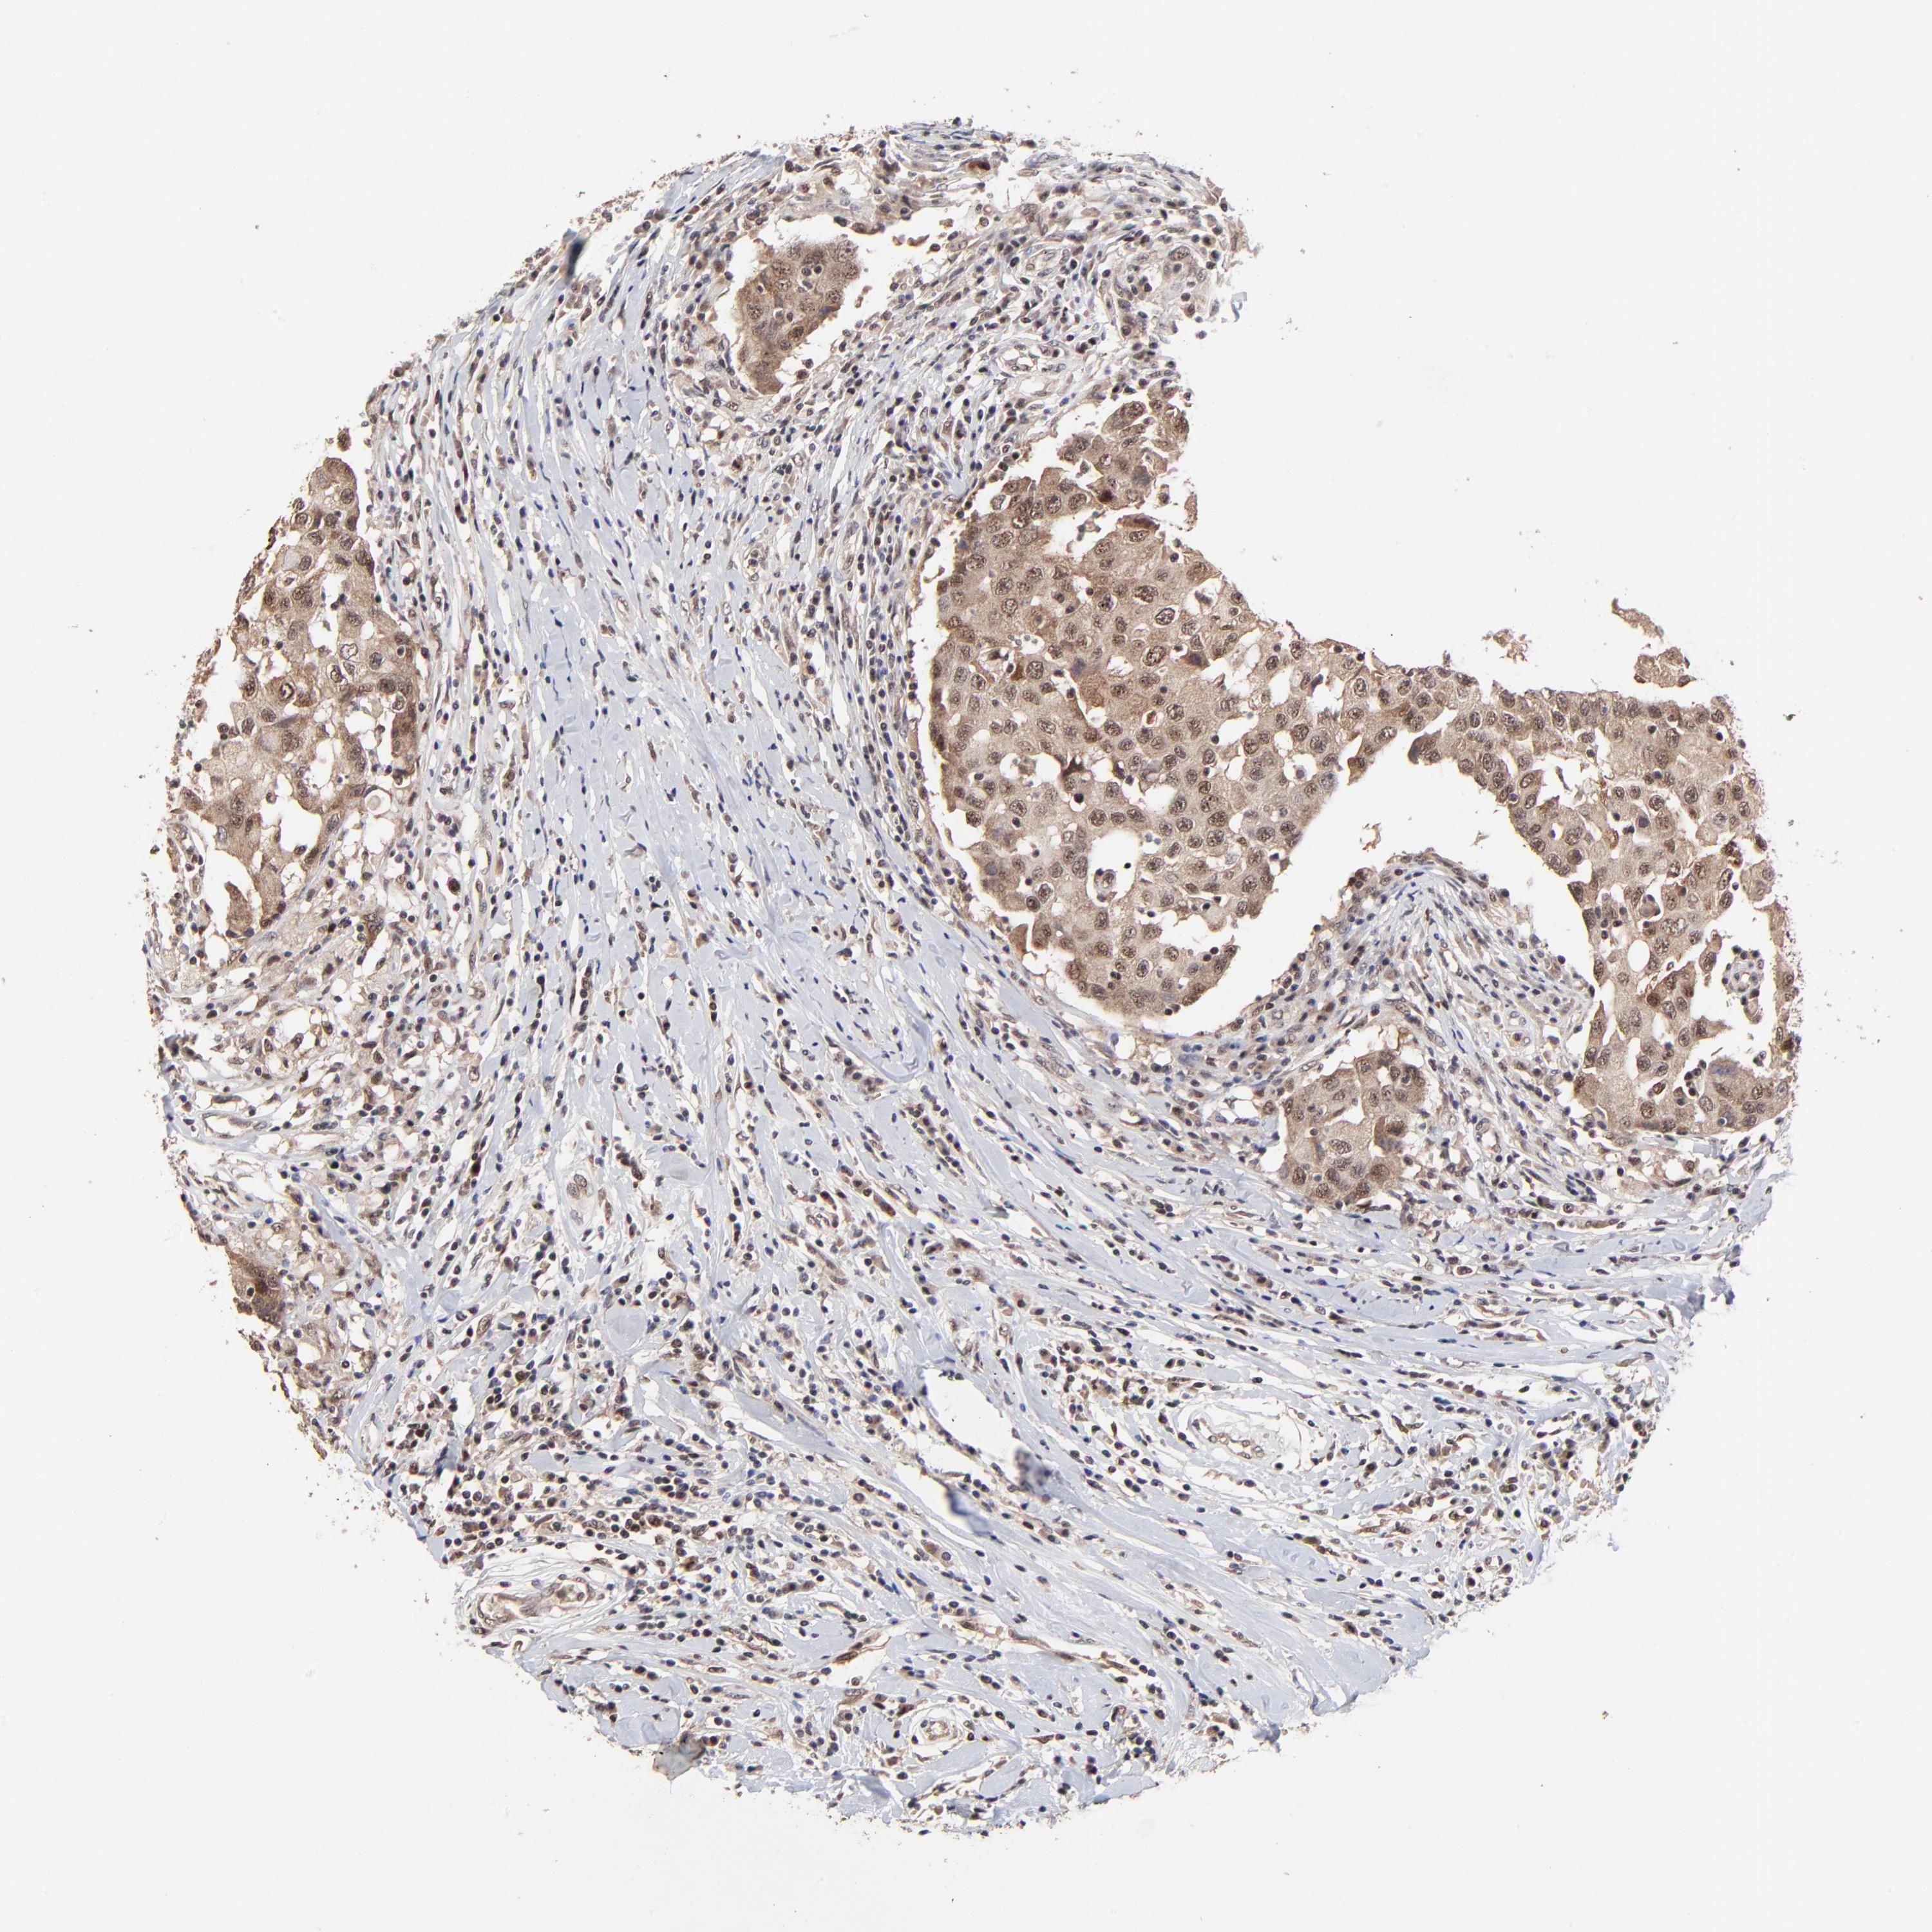

CANCER BREAST CANCER Show tissue menu

BRCA TCGA BRCA VALIDATION PROTEIN EXPRESSION